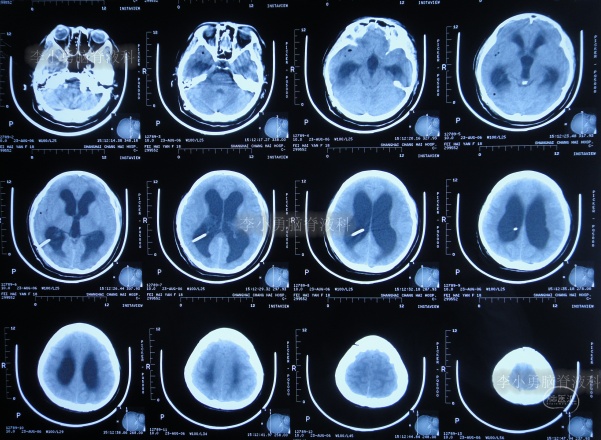

为治疗脑积水,于6天后即2006年8月15日就诊于上海的某三甲医院,入院时查头颅核磁示脑积水(图-3)。

图-3:2006年8月15日头颅核磁

图-4:2006年8月23日头颅CT

第1次脑室腹腔分流术后8个月即2007年5月1日,再次出现头晕头痛,在江苏省江阴市某医院查头颅CT(图-5)后传给给予手术医生,医生考虑是分流管堵塞。

图-5:2007年5月1日头颅CT

因分流管堵塞,2007年5月2日(第1次脑室腹腔分流术后8个月),第2次住入给予手术的医院,2007年5月5日(入院后3天),术后例行查头颅CT(图-6)后,加做了脑室腹腔分流术,但保留了原脑室分流管。

图-6:2007年5月5日头颅CT

图-7:2007年5月6日头颅CT上海

第2次脑室腹腔分流术后3月余即2007年8月15日,查头颅CT示未见异常(图-8)。

图-8:2007年8月15日头颅CT